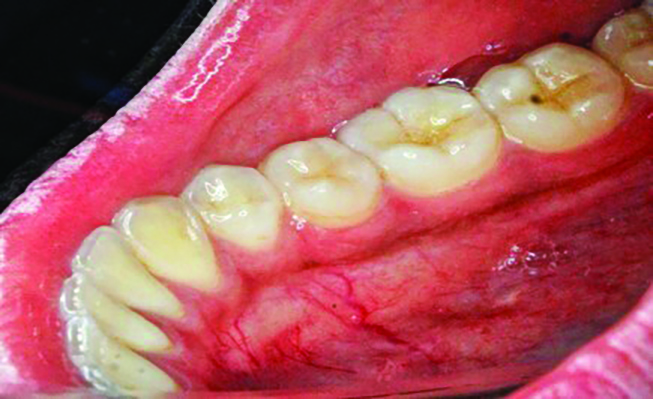

Table 1 presents descriptive statistics for the demographic characteristics of the participants: 83.33% of the study population were aged 18 to 24 years, while 16.66% were aged 25 to 30 years, and 20% of the participants were male while 80% were female, indicating a skewed distribution. Figure 4 through Figure 6 illustrate lingual AG of a representative male subject, and Figure 7 through Figure 9 depict that of a female subject. The mean, standard deviation, mode, median, and extremes for all the mandibular permanent teeth are recorded in Table 2. The extreme measurements were in the range of 0 mm to 10 mm, considering all teeth and subjects. The width of lingual AG varied with each tooth, with the mandibular first molar having the widest average width (6 mm ± 1.3 mm) followed closely by the second molar (5.8 mm ± 1.2 mm). The central incisors (0.5 mm ± 0.5 mm) showed the narrowest zone along with the highest maximum number of teeth without detectable AG (Table 3). The width of AG did not significantly differ between the sexes (Table 4). The overall indicative schematic of lingual AG is shown in Figure 10 and Figure 11.

Fig 4 through Fig 6. Lingual attached gingiva in a male subject: Fig 4 = left side.

Figure 4

Fig 5 = middle.

Figure 5

Fig 6 = right side.

Figure 6